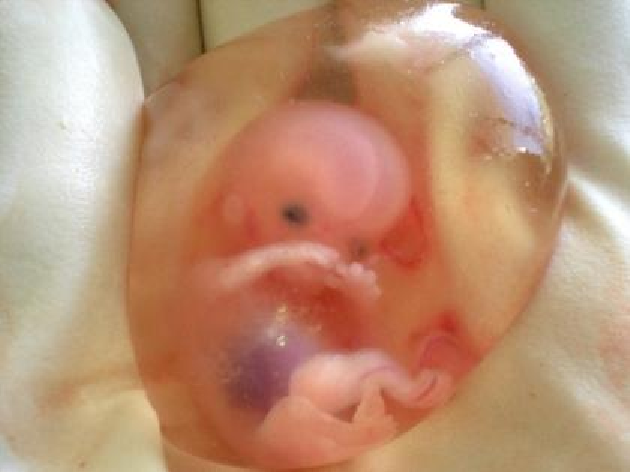

पूर्वी चंपारण जिला में एक ऐसा मामला सामने आया है जो मेडिकल साइंस के दुनिया के लिए रेयर एंड रेयरेस्ट केस होता है. एक मां के गर्भ में पल रहे बच्चे के पेट में बच्चा पल रहा था. जिसकी जानकारी उसके जन्म के 40 दिनों बाद उसकी चिकित्सीय जांच के बाद हुई. चिकित्सा जगत में इसे फिट्स इन फिटू अर्थात बच्चे के पेट में बच्चा के नाम से जाना जाता है. परिजनों के अनुसार जन्म के कुछ दिनों बाद एक बच्चे के पेट के नीचे गांठ जैसे फूलने लगा. परिजन बच्ची को लेकर मोतिहारी शहर स्थित रहमानिया मेडिकल सेंटर पहुंचे. जिसकी अल्ट्रासाउंड और अन्य जांच के बाद बच्चे के पेट में भ्रूण मिला.

बच्ची का चिकित्सकों ने सफल ऑपरेशन किया. बच्चे की स्थिति आज ठीक है और उसके स्वास्थ्य में सुधार हो रहा है. बच्ची का इलाज करने वाले रहमानिया मेडिकल सेंटर के डॉ. ओमर तबरेज के अनुसार मेडिकल भाषा में इसे ‘फिटस इन फिटू’ कहा जाता है और यह अपनी तरह का रेयर केस है जो पांच लाख में एक पाया जाता है. इसके अंदर जो चालीस दिन का बच्चा था. उसके अंदर एक और डेड भ्रूण पड़ा था तो वो एक लॉग प्रेजेंट कर रहा था जिसके कारण पेशेंट बच्चे को दिक्कत हो रहा था. लंग के तरफ इतने छोटे से उम्र में गांठ की तरह दिख रहा था.